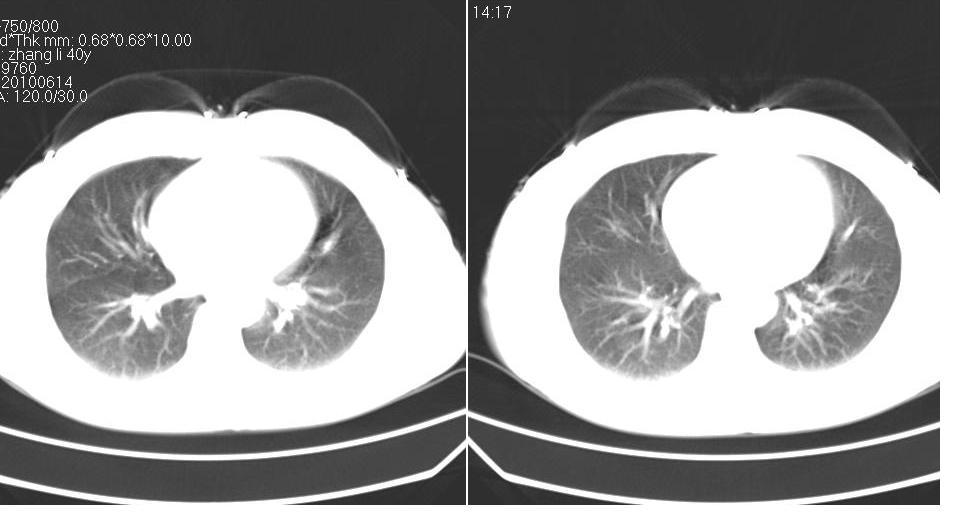

女 40岁,胸片体检发现右肺肿块,无任何症状。

下叶背段多发性小腺泡结节,考虑结核。

考虑侵润性结核

肺动静脉瘘可考虑,建议增强

典型结核表现

考虑右肺下叶背段继发性肺结核。